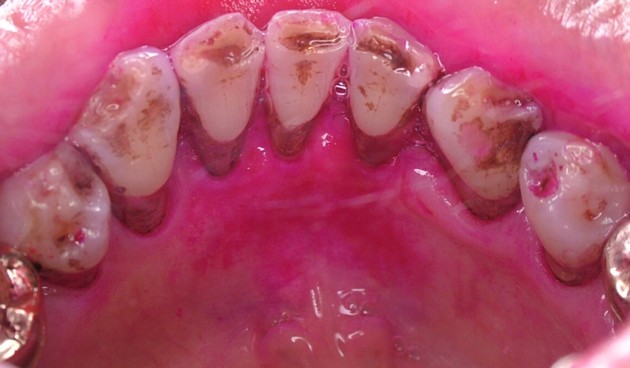

飲食物や嗜好品(コーヒーやお茶など)、体液中に含まれるメラニン色素などが歯面上に沈着したものです。直接的には為害作用はありませんが、審美性の問題や、あまり厚く沈着すると歯垢が付着しやすくなります。歯磨剤の的確な使用や歯科医師や歯科衛生士による歯冠研磨できれいになります。写真は下顎前歯の内側に見られる色素沈着です。